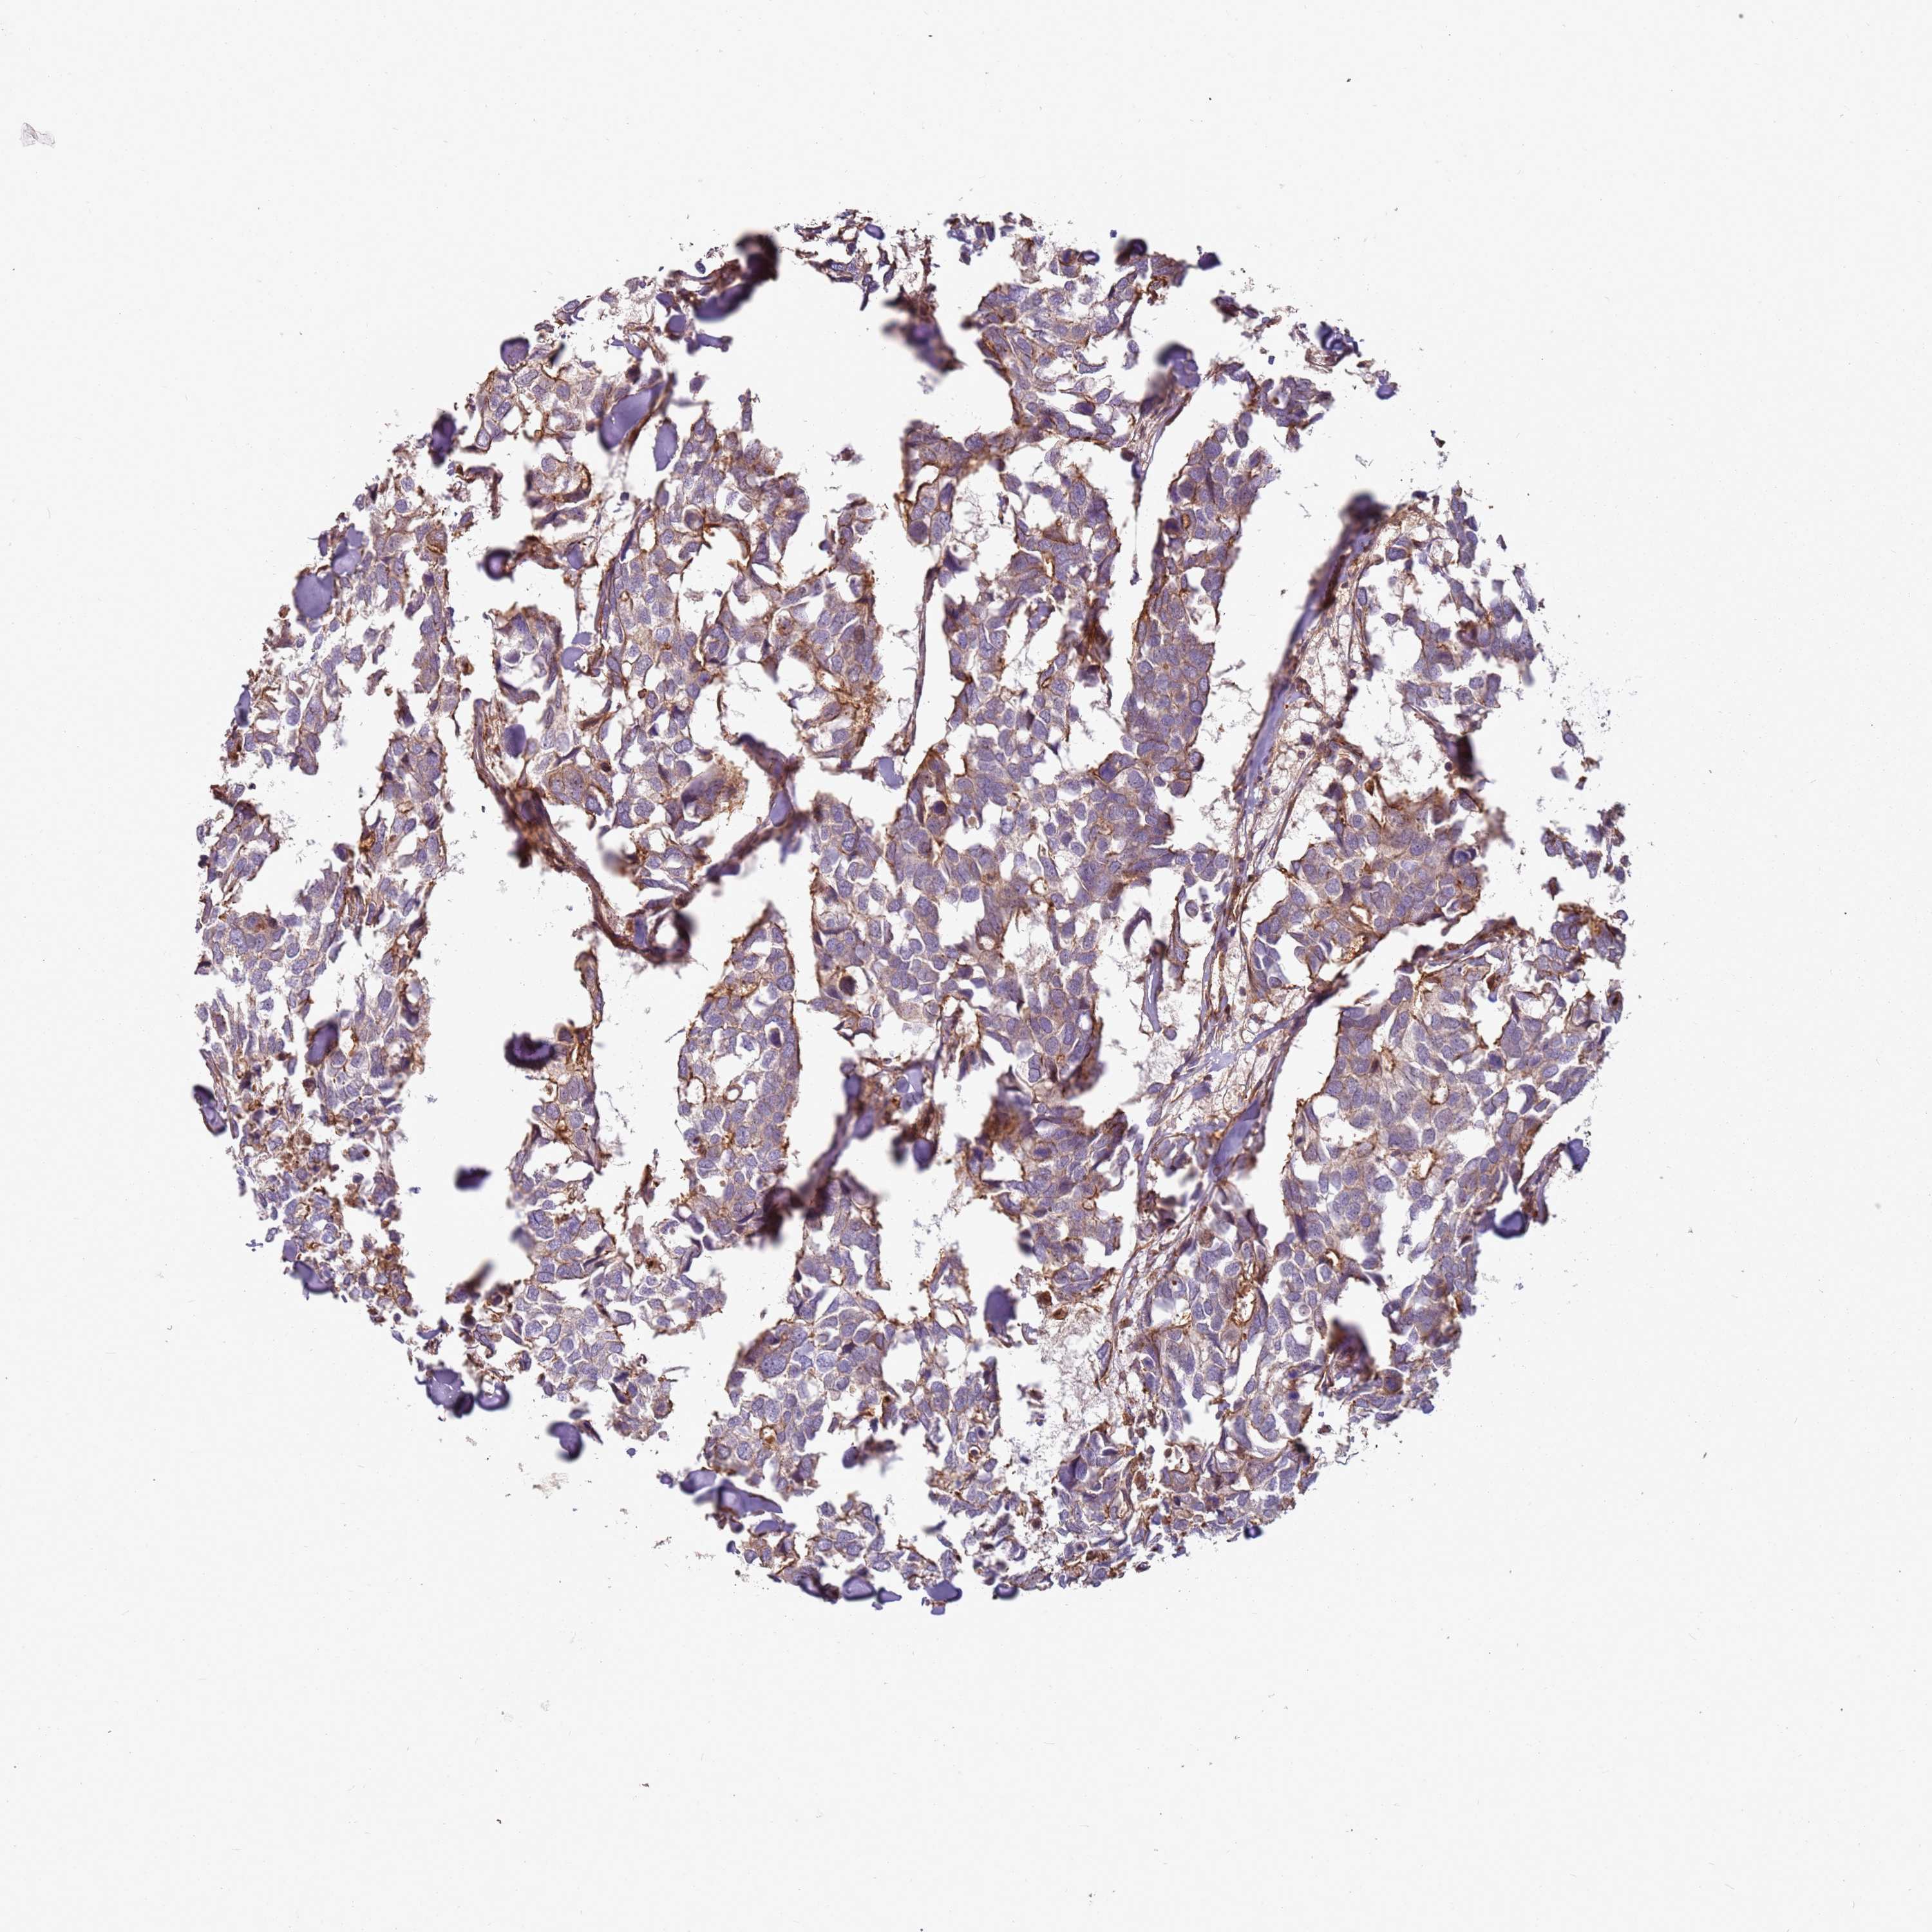

CANCER BREAST CANCER Show tissue menu

BRCA TCGA BRCA VALIDATION PROTEIN EXPRESSION